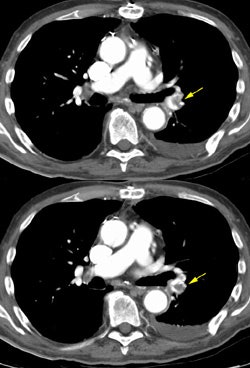

CT PE/DVT exam:

The example below demonstrates a pulmonary embolism in the left lower lobe pulmonary artery (Yellow arrows). Due to venous enhancement, clot can be seen within the right common femoral vein (Yellow arrow). The peripheral venous enhancement on this image obtained 3 minutes following intiation of the contrast infusion was approximately 90HU. The clot had an HU measurement of 44. (Click to view larger images if desired)